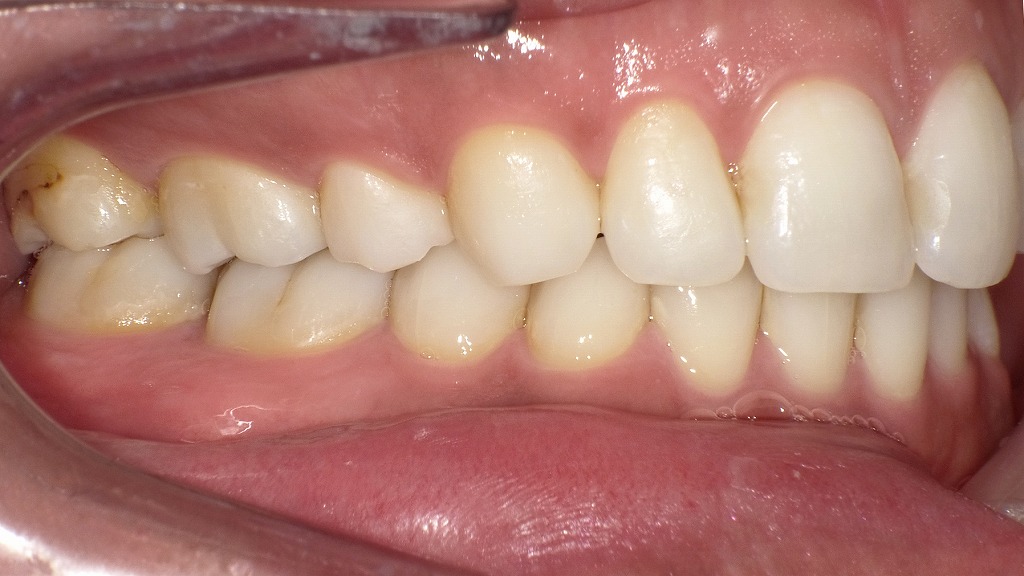

抜歯矯正後の側面観

これらの画像は、抜歯矯正後の側面観を示しています。全体的に咬合関係が良好で、機能的・審美的にもバランスが取れた状態です。

🦷 咬合(かみ合わせ)の特徴

- 上下の犬歯・小臼歯の咬み合わせが理想的で、Class I(正常咬合)に近い関係が確認できます。

- 上顎の歯が下顎の歯を適度に覆っており、オーバーバイト・オーバージェットともに適正範囲内です。

- 前歯から臼歯までスムーズな咬合平面が保たれています。

✨ 歯列と歯軸の整い方

- 上下の歯軸がきれいに整っており、歯列弓が自然なカーブを描いています。

- 上顎前歯の後退により、口元の突出感が改善されています。

- 臼歯部の咬合接触も良好で、咀嚼機能が安定していることがうかがえます。

💬 総合コメント

抜歯矯正により、前歯の位置と奥歯の咬合関係が調和し、理想的な横顔ラインを形成しています。

見た目の美しさだけでなく、噛む力のバランスや機能面でも優れた結果が得られている状態です。